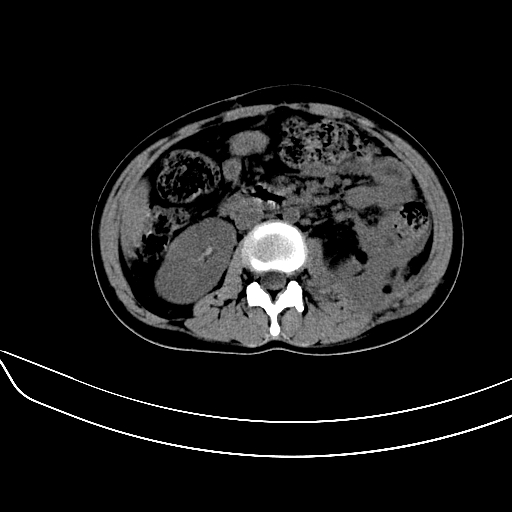

女,22岁,临床以糖尿病等病史入院,两年前有妊娠合并胰腺炎史,现有多饮、多尿、咳嗽、咳痰、左腰痛、发热等。因多种原因没做增强。

2、脾包膜下血肿、左侧腹膜后血肿(可能为特发性)。

肝、脾增大,内见多发低密度影,少量腹水,左侧肾周筋膜增厚,结合病人糖尿病史,有左腰痛、发热,考虑:糖尿病激发肝脾病变(梗塞?),左侧肾周感染,建议进一步检查。

真可惜,这么年轻就重病缠身,患者肝内,脾,肾,左下肺,左腰大肌均见病变,结合病史考虑感染可能性大。

左肾周感染,腰大肌脓肿,肝脾脓肿?不能增强,就来个mri。